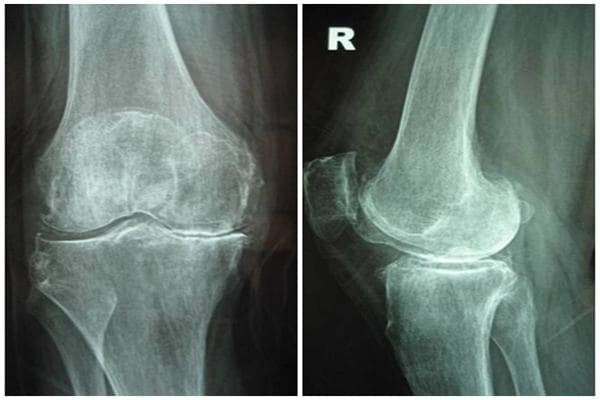

Vỡ xương bánh chè có đi lại được không? Vỡ xương bánh chè là một loại chấn thương khá phổ biến thường xảy ra khi người bệnh ngã gập gối xuống đất. Lúc này khớp gối sưng to, đau chói, không thể tự co duỗi được. Khi ấn vào có cảm giác đau, khám thấy dấu hiệu bập bềnh xương bánh chè.

Phương pháp này thường được áp dụng khi vỡ xương bánh chè dạng nứt rạn, không di lệch (2 mảnh và mặt khớp bánh chè-lồi cầu đùi không bị khấp khểnh); người bệnh cao tuổi không đi đứng được hoặc có bệnh nội khoa nặng kèm theo. Tùy từng trường hợp có thể được bó bột.

Thường được chỉ định khi vỡ xương bánh chè, 2 phần vỡ rời xa nhau quá 4mm, gãy vụn khi diện khớp của các mảnh gãy khấp khểnh hoặc có mảnh rời di lệch vào khớp gối. Bác sĩ có thể mổ buộc vòng chỉ thép, mổ buộc xương chữ U, mổ bắt vít, mổ néo ép. Trong trường hợp vỡ vụn quá, cần mổ lấy bỏ xương bánh chè.